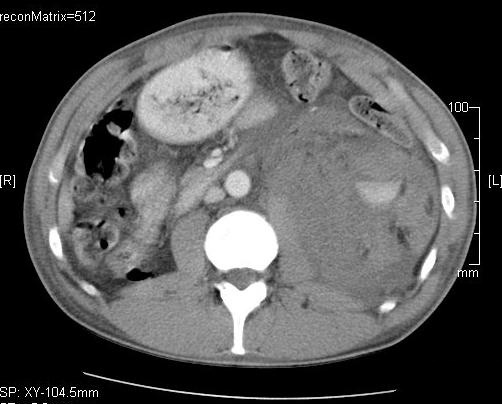

Compared to the surgical methods of past, nowadays these cystic lesions can be successfully treated percutaneously with alcoholic cyst sclerotization. (Figures 26., 27.).

Image

Figure 26. – Percutaneous ethanol cyst sclerotization ( filling up of the cyst before the sclerotization)

A

B

Figure 27. – US and CT examinations before percutaneous ethanol sclerotization (A: US examination, B: CT examination)

The puncture of the cyst is usually guided with US (rarely with CT). The puncturing needs to take place from the parenchymal side of the cyst. When its contents are removed the empty cavity is filled up with diluted contrast material to ensure that there is no contrast leakage to the surroundings. The 96% ethanol is only injected after the contrast material has been removed and no leakage was found. (The volume of the alcohol should not exceed 50-60% of the cyst or 100 ml.)